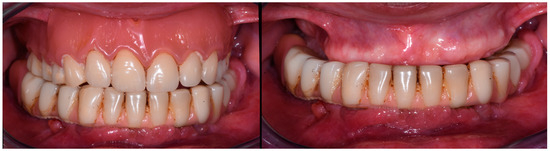

3.1. Case Report